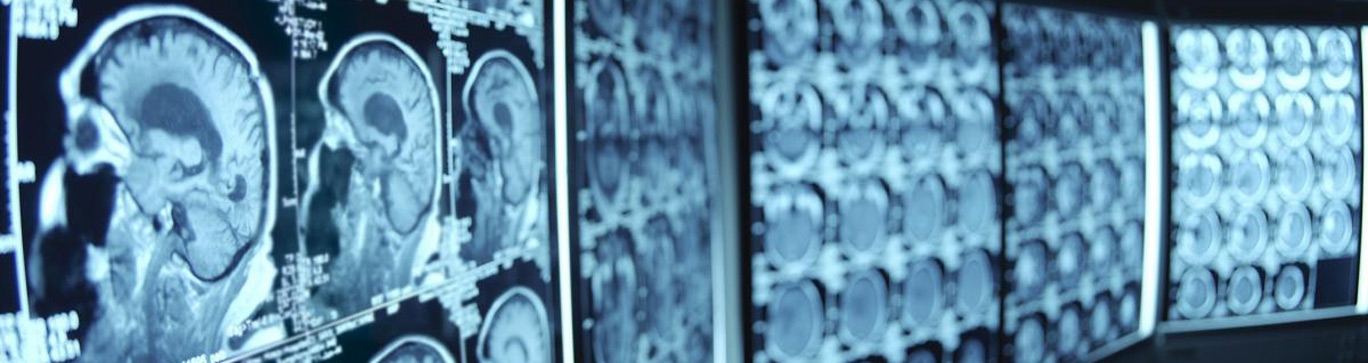

We supplement our clinical expertise in diagnosing the presence and extent of diseases through the use of radiation, ultrasound, and magnetic resonance as diagnostic, therapeutic, and research tools.

• MRI (1.5 Tesla)